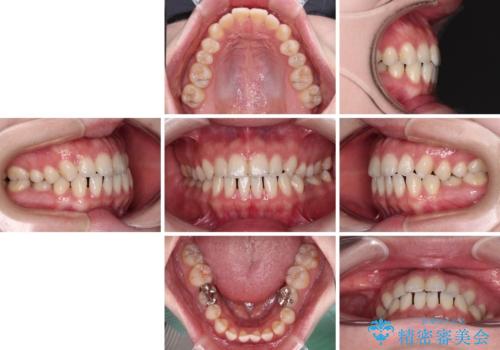

すきっ歯をインビザラインできれいな歯並びに改善

- 1年5ヶ月

- 5-10回

- 前歯の隙間を気にして来院された患者様です。

隙間や叢生の程度はそれほど著しいものではなかったので、インビザラインでもワイヤー矯正でも対応可能でしたが、極力目立たない装置を希望されたため、インビザラインにて矯正治療を行うこととしました。

すきっ歯の原因は色々ありますが、嚥下や発音時の舌突出癖が大きな原因となることがあります。

こちらの患者様も強い突出癖があったため、舌のトレーニング指導を行いました。